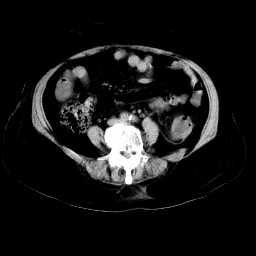

以下是引用余辉在2008-11-9 9:47:00的发言:[br]各层面均可见降结肠管壁增厚,管腔狭窄,中部层面可见管壁明显增厚区,结合病史多考虑降结肠癌,溃疡性结肠炎不除外,建议进一步检查